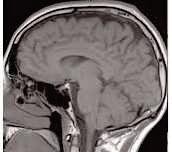

In the past few decades, a team of researchers has identified biological pathways leading to neurodegenerative diseases and developed promising molecular agents to target them. However, the translation of these findings into clinically approved treatments has progressed at a much slower rate, in part because of the challenges scientists face in delivering therapeutics across the blood-brain barrier (BBB) and into the brain. To facilitate successful delivery of therapeutic agents to the brain, a team of bioengineers, physicians, and collaborators at Brigham and Women's Hospital and Boston Children’s Hospital created a nanoparticle platform, which can facilitate therapeutically effective delivery of encapsulated agents in mice with a physically breached or intact BBB.

In a mouse model of traumatic brain injury (TBI), they observed that the delivery system showed three times more accumulation in the brain than conventional methods of delivery and was therapeutically effective as well, which could open possibilities for the treatment of numerous neurological disorders.

The findings published in Science Advances shows that previously developed approaches for delivering therapeutics into the brain after TBI rely on the short window of time after a physical injury to the head when the BBB is temporarily breached. However, after the BBB is repaired within a few weeks, physicians lack tools for effective drug delivery.